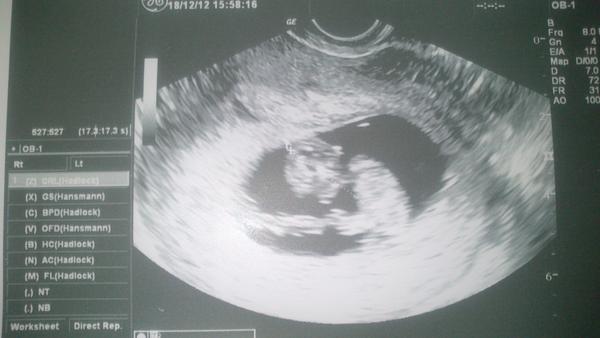

Drobček má 3,3 cm zodpovedá 10tt + 1, čiže o jeden deň je väčší, ako sme podľa termínu. Na sone bol pokojný, vôbec sa ani nepohol, len srdiečko bilo - ale sono bolo strašne krátke, ani nie 10 sekúnd, tak ho možno nestihlo zobudiť. Doktor bol odmeraný, nechcel dnu pustiť mm, vraj je to neetické, keď sa robí vaginálne sono, ale potom, keď som si vypýtala fotku, tak mi povedal, že ho môžem zavolať a pustil mu ten 5 sekundový film s naším drobčekom.

A čo ma úplne dorazilo, tak mi vypočítal termín podľa MS, ktorý mi dal do tehu knižky, hoci vôbec nezodpovedá termínu podľa IVF, ale že jeho to nezaujíma, on to bude počítať podľa MS. Takže už mám aj ja tehu knižku. 🙂 Tak dobrú noc, zajtra sa vidíme.